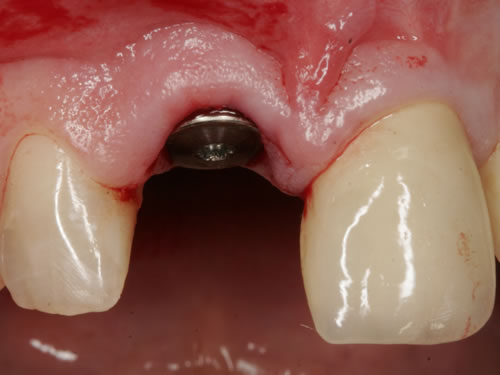

Häufig führt ein Zahnverlust zu einem Verlust von Knochen (Hartgewebe) und der bedeckenden Schleimhaut (Weichgewebe). Besonders im sichtbaren ästhetisch sensiblen Bereich ist es aber notwendig, dass sowohl Hart- als auch Weichgewebe so wiederhergestellt wird, dass im Idealfall das Zahnimplantat mit seiner Krone dem Aussehen des ehemaligen gesunden Zahn entspricht. Als Erfolgskriterien werden aus zahntechnischer Sicht die Form, Farbe und Größe der individuellen Krone angesehen. Aus medizinischer Sicht gibt es wichtige Erfolgskriterien, die die Implantatposition, die Implantatlänge, den Implantatdurchmesser, den Zahnfleischrand im Vergleich zum Nachbarzahn und die Zahnfleischpapillen zwischen den Zähnen beinhalten. Zusätzlich braucht man ein zahntechnisches Labor, das mit der Keramikverarbeitung ein natürliches Aussehen gestalten kann. Nur, wenn alle Parameter perfekt sind, ist das Ergebnis perfekt. Das macht den Einzelzahnersatz im Oberkieferfrontzahngebiet zu einer echten Herausforderung.

Nach der Entfernung von Zähnen kommt es schnell zu Knochenverlust (Resorptionen) und entsprechendem Verlust von Schleimhaut. Die Schleimhaut kann durch bestimmte Operationstechniken wiederhergestellt werden, in dem man freie oder gestielte Bindegewebstransplantate z. B. vom Gaumen entnimmt und das fehlende Material so ersetzt. Das Weichgewebe kann in unterschiedlichen Behandlungsphasen korrigiert werden. In vielen Fällen wird es während der Implantation oder bei der Freilegung verbessert. Manchmal müssen Feinkorrekturen auch nach Eingliederung der fertig gestellten Krone erfolgen, wenn ästhetische Einbußen vorliegen. Häufig hat die Zahnfleischkorrektur auch noch einmal die Änderung der endgültigen Krone zur Folge (Abb. 7.14, 7.15).

Aus der bekannten Tatsache, dass Knochen- und Weichgewebsverlust nach Zahnentfernungen stattfinden und dass der Verlust grösser ist, je länger die Entfernung des Zahnes her ist, wurde die zeitnahe Implantation überlegt. So kann das Hart- und Weichgewebe durch das neue gesetzte Implantat gestützt und muss nicht zu einem späteren Zeitpunkt ersetzt werden. Für eine Sofortimplantation müssen aber wichtige Kriterien erfüllt sein. Hierzu zählen entzündungsfreier Zahnverlust, gute und dicke Zahnfleischform und keine entzündlichen Veränderungen des Zahnhalteapparates. Wenn diese wichtigen Parameter erfüllt sind, dann ist eine Sofortimplantation möglich. Leider sind die Voraussetzungen nur in sehr wenigen Fällen so, da selten gesunde, entzündungsfreie Zähne entfernt werden. In der Bildergalerie wurde ein tief kariöser Zahn ideal entfernt, ein Implantat als Sofortimplantat eingesetzt und mit einer provisorischen Kunststoffkrone versorgt. Nach Abheilung erfolgte die definitive prothetische Versorgung mit einer Vollkeramikkrone (Abb. 7.16, 7.17).

Abb. 7.16: Sofortimplantat eines oberen mittleren Schneidezahnes, mit eingebautem Implantataufbau.

Abb. 7.17: Zementierte definitive Krone nach Einwachsen des Implantates (3 Monate später).